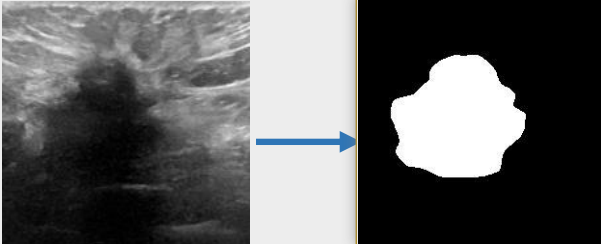

U-KAN与其它图像分割算法一样,将图片数据送入模型后,依次通过预处理、特征提取,最后经过卷积预测出像素类别实现分割。

## 数据集

`BUSI(Breast Ultrasound Image)`

- https://www.kaggle.com/datasets/aryashah2k/breast-ultrasound-images-dataset

本项目无需下载原始数据集,采用U-KAN作者提供的预处理数据[pre-processed dataset](https://mycuhk-my.sharepoint.com/:f:/g/personal/1155206760_link_cuhk_edu_hk/ErDlT-t0WoBNlKhBlbYfReYB-iviSCmkNRb1GqZ90oYjJA?e=hrPNWD) 即可。